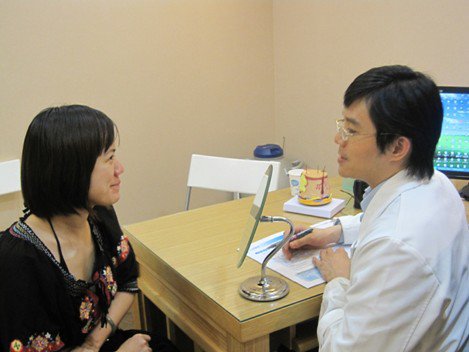

看這張圖,這是我第一次去光澤跟王醫師呈現對峙狀態的我,鼻子又油又紅到什麼程度。

看這張圖,這是我第一次去光澤跟王醫師呈現對峙狀態的我,鼻子又油又紅到什麼程度。